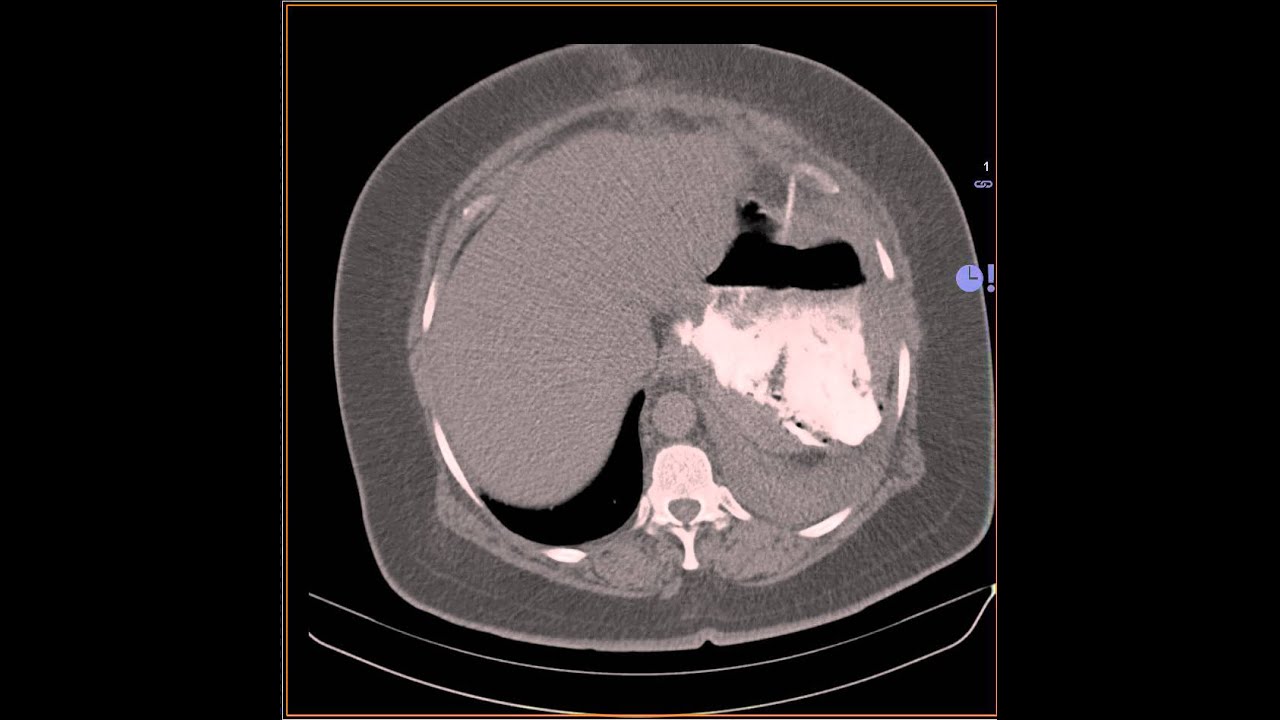

Post sleeve gastrectomy leak with abscess Image Post Sleeve Gastrectomy Leak Radiology Sleeve gastrectomy is a bariatric surgical procedure involving resection of the greater curvature of the fundus and body of the stomach to leave approximately 15% of the. It has recently gained in popularity because of a low complication rate, satisfactory resolution of comorbidities, and excellent. This classification recognizes 4 types of leak based on the size and location of fluid. Post Sleeve Gastrectomy Leak Radiology.

sleeve gastrectomy CT leak YouTube Post Sleeve Gastrectomy Leak Radiology Pain after eating a light meal. Tender upper abdomen with raised. Sleeve gastrectomy for weight loss 1 week earlier. Sleeve gastrectomy (sg) is the most commonly performed bariatric procedure in the us [1].one of the most common. It has recently gained in popularity because of a low complication rate, satisfactory resolution of comorbidities, and excellent. In addition, we describe the. Post Sleeve Gastrectomy Leak Radiology.